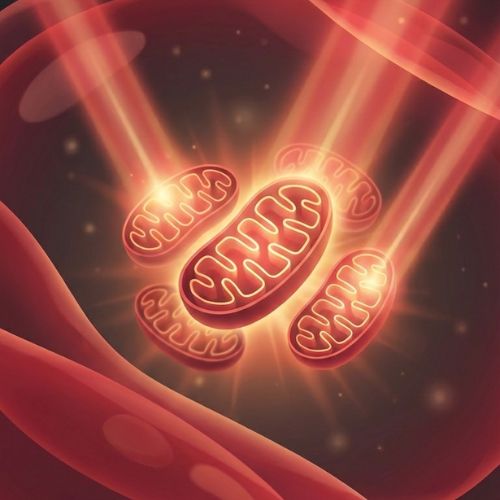

Red light therapy (also known as photobiomodulation) uses specific wavelengths of light to stimulate your cells' natural repair processes. Red light (660nm) targets surface tissue and inflammation, while near-infrared light (850nm) penetrates deeper — reaching joints, muscles, and bone-level structures. It's non-invasive, drug-free, and backed by over 3,000 published studies.

The mat delivers 1,370 clinical-grade LEDs across your entire body while you lie down. The dual wavelengths (660nm + 850nm) are absorbed by your cells, boosting mitochondrial ATP production — your body's natural repair fuel. Over time, this calms inflammation, eases stiffness, and accelerates recovery.

Is this device backed by science?

Absolutely. Photobiomodulation — the science behind red and near-infrared light therapy — has been studied in over 3,000 peer-reviewed publications. The wavelengths Pavra uses (660nm and 850nm) are the most widely researched for inflammation, pain reduction, and cellular repair. This isn't new or experimental — it's been used in clinical and research settings for decades.